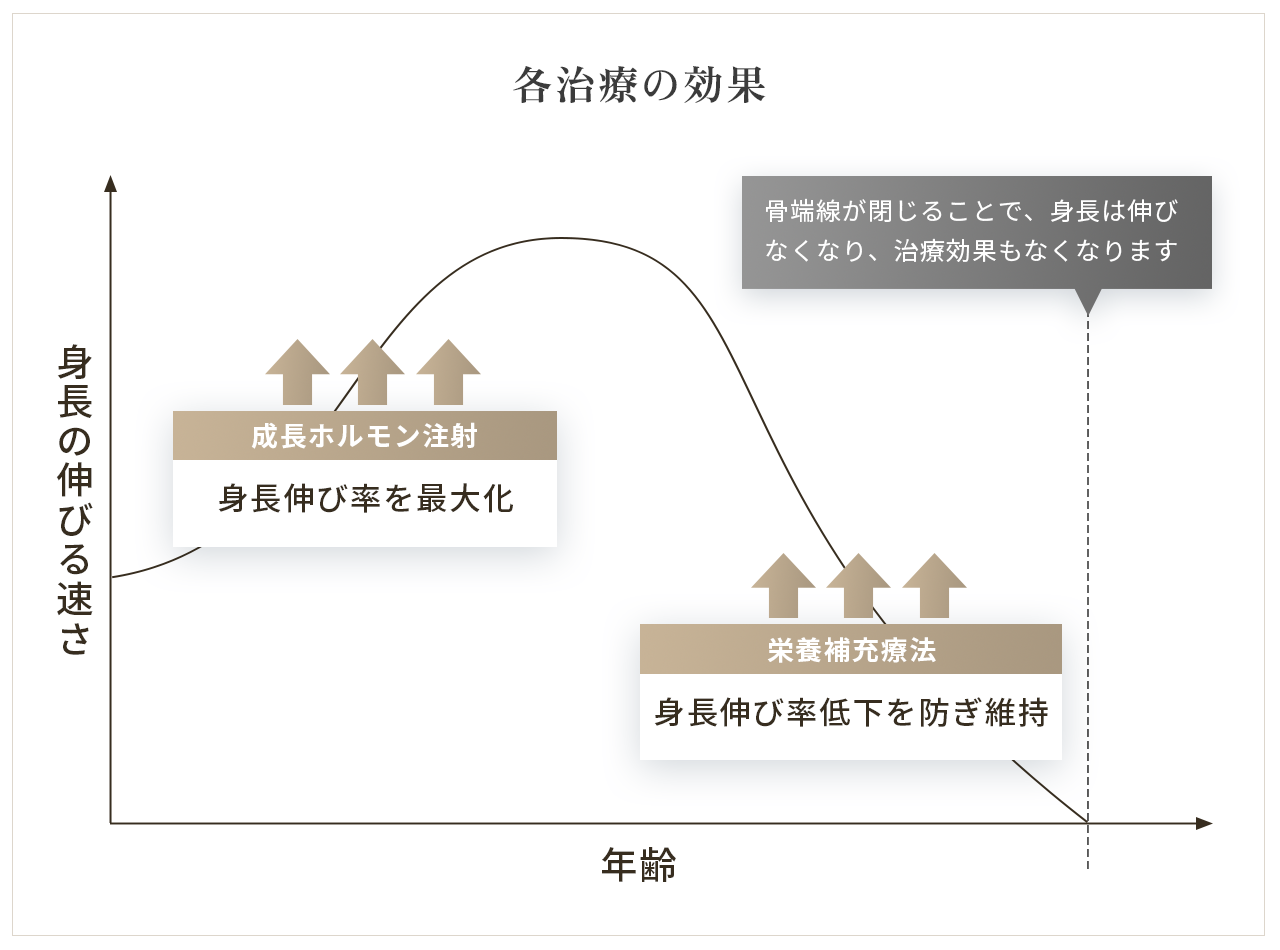

成長ホルモン注射

成長ホルモン療法は、通常、毎日または週1回の自己注射によって行います。

サプリメントによる栄養素の補充

当院では、成長ホルモン療法に加え、骨や筋肉の発達に欠かせない栄養素をサプリメントで補う「栄養補充療法」を必要に応じて併用しています。ホルモンを投与するだけでなく、体がしっかりと成長反応を起こせるように、内側からのサポートも重視しています。

カルシウム・マグネシウム・亜鉛・ビタミンDなど、骨端線や骨の形成に必要な成分をバランスよく配合。これらの栄養素が成長ホルモンの働きを助けることで、骨端線の細胞増殖を効率的に促進します。その結果、身長の伸び率の低下を防ぎ、効果を長く維持することにつながります。

成長ホルモンと栄養素の相乗効果により、成長期という限られた時間を最大限に活かせるようサポートいたします。